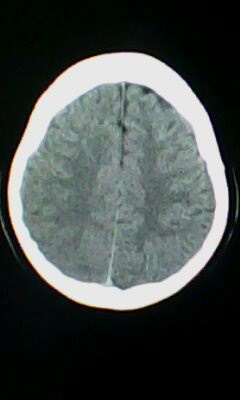

颅脑ct轴位平扫颅内未见明确异常。

颅脑ct轴位平扫颅内未见明确异常,建议mri。